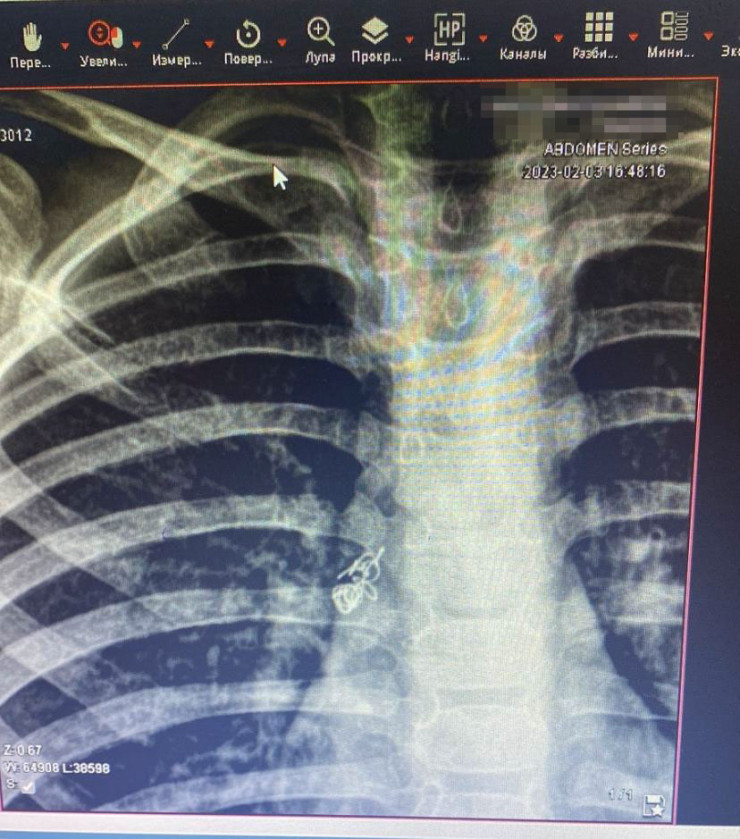

"Ребенок осмотрен специалистами, проведена рентгенография грудной клетки. На рентгенограмме выявили инородное тело правого бронха. Он был госпитализирован, проведена подготовка к манипуляции. Под общим наркозом проведена жесткая трахебронхоскопия. Под визуальным контролем инородное тело (пружинка) обнаружено в правом главном бронхе", - сообщили в пресс-службе ДГКБ № 2.